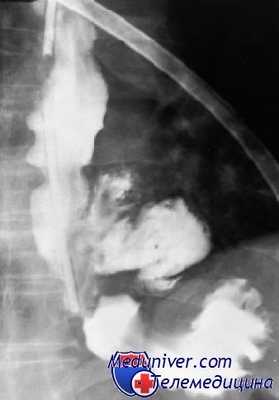

Затем пациентам с подозрением на перфорацию пищевода назначается консультация врача-эндоскописта. Необходимо провести эзофагоскопию жестким эндоскопом (не раздувая пищевод воздухом) для выяснения точного расположения и конфигурации перфорации пищевода. Во время эзофагоскопии производится эвакуация отделяемого из патологической полости в околопищеводной клетчатке (гноя, пищевых масс, контрастного вещества и т. д.). Кроме того, в ходе эндоскопии предоставляется возможность безопасно провести зонд в желудок.